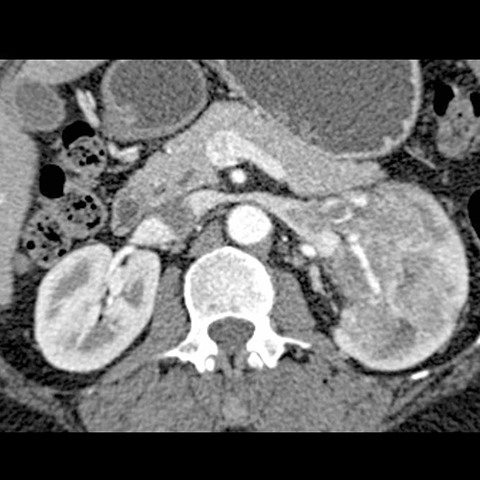

67-year-old male with flank mass and hematuria [4 of 4]